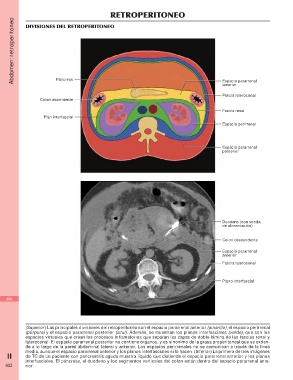

Divisiones del retroperitoneo

Páncreas Espacio pararrenal

Colon ascendente anterior

Fascia lateroconal

Plan interfascial Fascia renal

Espacio perirrenal

Espacio pararrenal

posterior

Duodeno (con sonda

de alimentación)

Colon descendente

anterior

Plano interfascial

(Superior) Las principales divisiones del retroperitoneo son el espacio pararrenal anterior (amarillo), el espacio perirrenal

(púrpura) y el espacio pararrenal posterior (azul). Además, se muestran los planos interfasciales (verde), que son los

espacios virtuales que crean los procesos inflamatorios que separan las capas de doble lámina de las fascias renal y

lateroconal. El espacio pararrenal posterior no contiene órganos, y es sinónimo de la grasa properitoneal que se extien-

de a lo largo de la pared abdominal lateral y anterior. Los espacios perirrenales no se comunican a través de la línea

II media, aunque el espacio pararrenal anterior y los planos interfasciales sí lo hacen. (Inferior) La primera de tres imágenes

de TC de un paciente con pancreatitis aguda muestra líquido que distiende el espacio pararrenal anterior y los planos

interfasciales. El páncreas, el duodeno y los segmentos verticales del colon están dentro del espacio pararrenal ante-

402 rior.